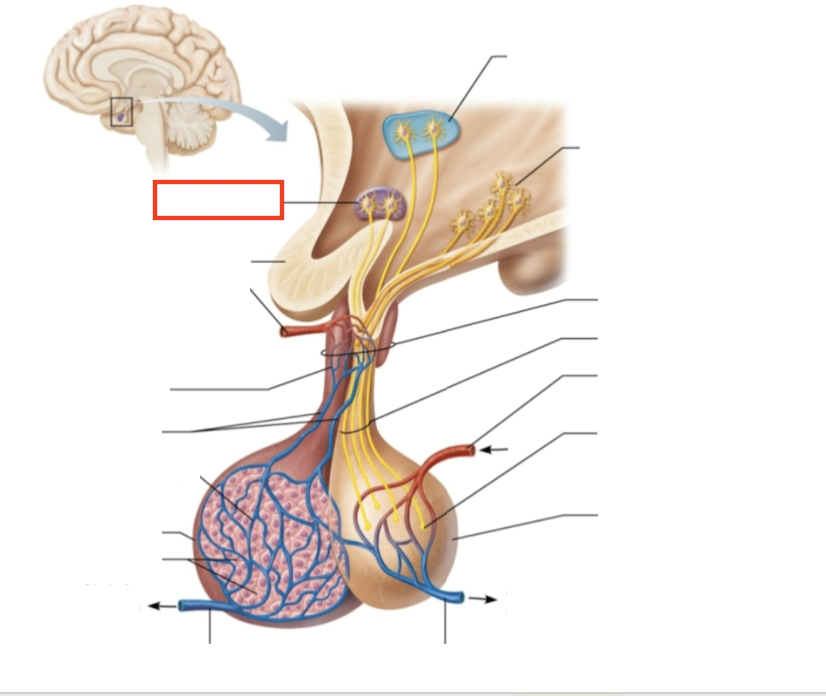

testes (male)

What structure is highlighted?

hypothalamic neurons in the paraventricular nuclei

What structure is highlighted?

neurons in the ventral hypothalamus

What structure is highlighted?

infundibulum (connecting stalk)

What structure is highlighted?

hypothalamic-hypophyseal tract

What structure is highlighted?

inferior hypophyseal artery

What structure is highlighted?

neurohypophysis (storage area for hypothalamic hormones)

What structure is highlighted?

posterior pituitary

What molecules are produced here?

oxytocin, ADH

What structure is highlighted?

venule

What structure is highlighted?

venule

What molecules are produced here?

TSH, FSH, LH, ACTH, GH, PRL

What structure is highlighted?

secretory cells of adenohypophysis

What structure is highlighted?

anterior pituitary

What structure is highlighted?

secondary capillary plexus

What structure is highlighted?

hypophyseal portal veins

What structure is highlighted?

primary capillary plexus

What structure is highlighted?

superior hypophyseal artery

What structure is highlighted?

superior hypophyseal artery

What structure is highlighted?

optic chiasma

What structure is highlighted?

hypothalamic neurons in the supraoptic nuclei

What are the target organs and effects of testosterone?

most cells of the body; promotes the maturation of the male reproductive organs, the development of secondary sex characteristics, sperm production, and sex drive

What hormone is produced by the testes?

testosterone

What stimulates testosterone production?

LH and FSH